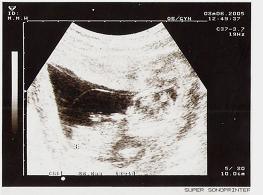

12週產檢

時間:2005.08.06(星期六)

地點:淡水馬偕產科一診

超音波中,小B的手腳都長出來囉

而且會活潑地揮舞著,好可愛喔

頭部比例看起來頗大

側面看上去,似乎鼻子不高耶,有點擔心

老公是第一次陪檢看超音波

他也很高興

直覺告訴他這是小男生

醫生幫小B量身高,頭部到臀部尺寸6.8公分(腳曲起來無法量)

雖然目前小B不到1KG,但身為他娘的我卻肥了2KG

根據醫院令我懷疑是否故障的電子體重計測量,目前本人體重54.4